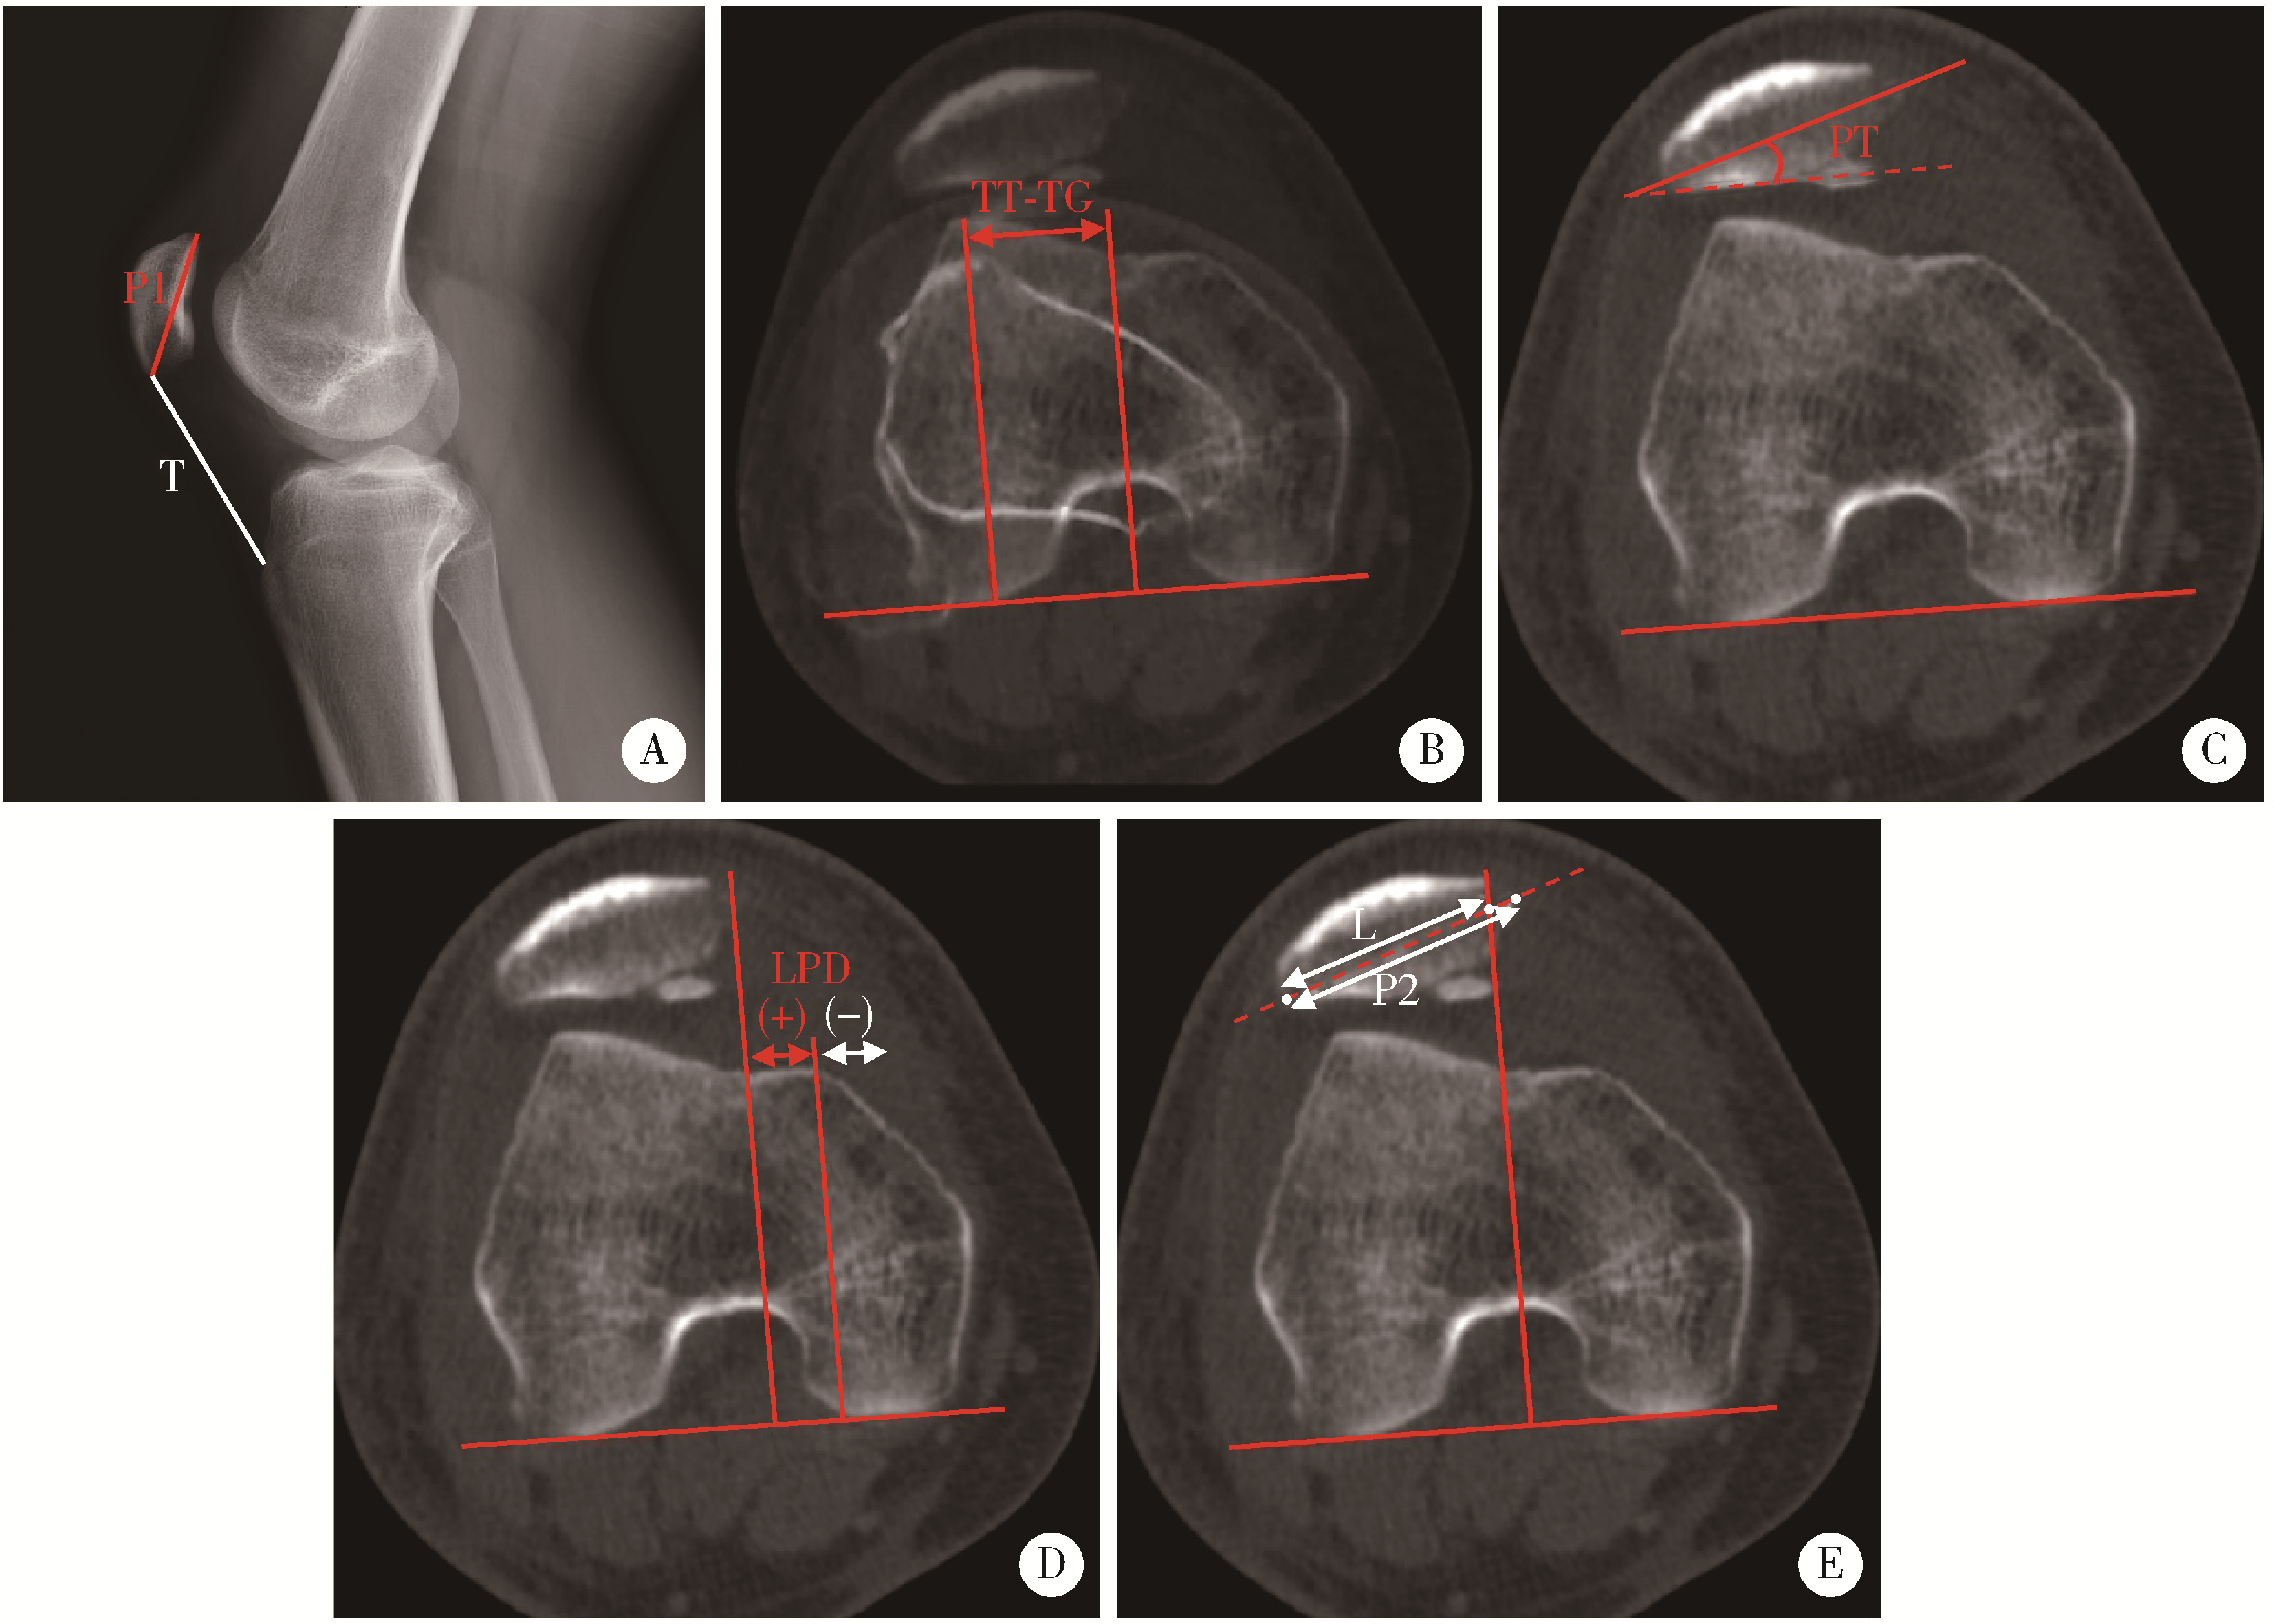

2.5 影像学评估

术后CT评估显示,髌骨倾斜角平均为9.8°±6.0°(范围1.5°~32.8°),髌骨外移距离平均为(-8.7±7.1) mm(范围-19.6~8.9 mm),BSO比值为0.6±0.2(范围0.6~1.9),较术前均有显著改善(P < 0.001,表 6)。这些参数的显著变化表明镜下MPFC重建能够纠正脱位后髌骨外倾外移状态,有效恢复髌股关节对位关系(图 4)。

图4 内侧髌股复合体重建前后髌股关节轴位CT对比

Figure 4 Comparison of axial CT scans of the patellofemoral joint before and after MPFC reconstruction

Patient 1 was a 17-year-old male diagnosed with recurrent patellar dislocation of the right knee. Preoperative CT scan showed significant patellar tilt and lateral displacement, which were both corrected on postoperative scan. Patient 2 was a 16-year-old male diagnosed with recurrent patellar dislocation of the right knee. Preoperative CT scan demonstrated a dislocated patella with remarkable tilt and lateral translation, while the patellofemoral congruence was restored on postoperative scan. CT, computed tomography; MPFC, medial patellofemoral complex reconstruction.